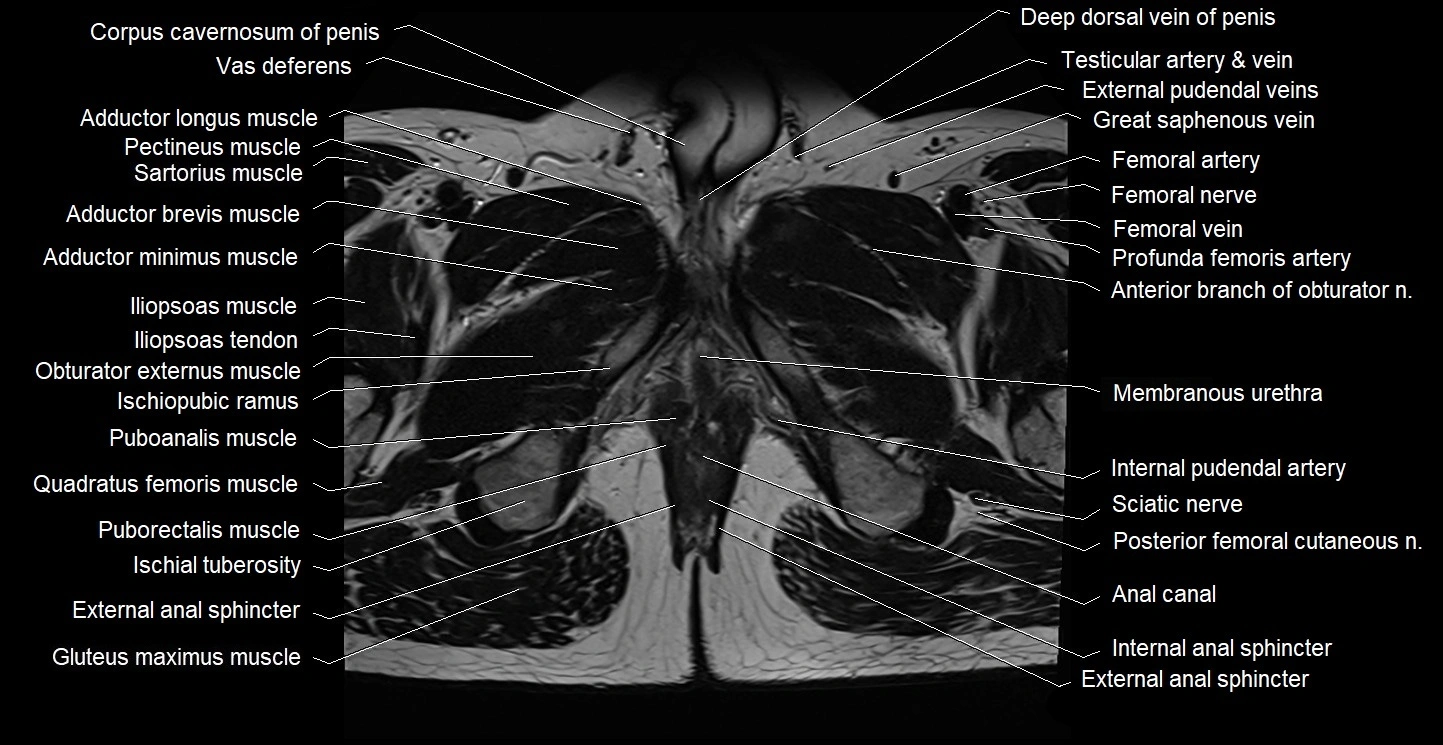

- Anal canal

- Deep dorsal vein of penis

- External anal sphincter

- External urethral sphincter (male)

- Femoral artery

- Femoral nerve

- Femoral vein

- Gluteus maximus muscle

- Iliopsoas muscle

- Iliopsoas tendon

- Internal anal sphincter

- Internal pudendal artery

- Ischial tuberosity

- Ischiopubic ramus

- Levator ani muscle

- Membranous urethra

- Obturator externus muscle

- Obturator internus muscle

- Posterior femoral cutaneous nerve

- Puboanalis muscle

- Puborectalis muscle

- Quadratus femoris muscle

- Sciatic nerve

- Vas deferens